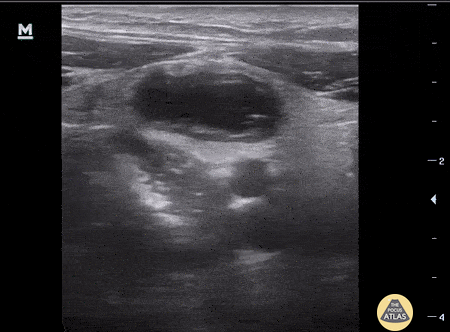

Pediatric appendicitis: 4mm appendicolith in mid-appendix with surrounding edema. Aaron Inouye, PA-C Emergency Medicine. North Canyon Medical Center, Idaho @PAintheED